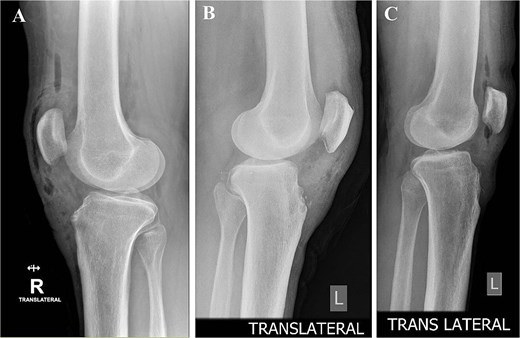

On physical exam, they had localized tenderness at the tibial tubercle, pain when kneeling, and discomfort with resisted knee extension. X-rays showed persistent ossicles in all cases, and we followed up with MRI to rule out any other underlying issues (Fig. 1).

Preoperative lateral radiographs showing persistent tibial tubercle ossicles. (A) Right knee for first case. (B) Left knee for second case. (C) Left knee for third case.

The mean time to return to unrestricted sports was 5 weeks (range, 4–6 weeks). Radiographs confirmed complete ossicle excision (Fig. 10), and all three patients resumed pre-injury levels. No recurrence or secondary procedures were needed. The Kujala scores improved from 83 to 99, 81 to 100, and 85 to 100, respectively.

Postoperative lateral radiographs confirming complete excision and smooth tibial tubercle contour. (A) Right knee, case 1. (B) Left knee, case 2. (C) Left knee, case 3.